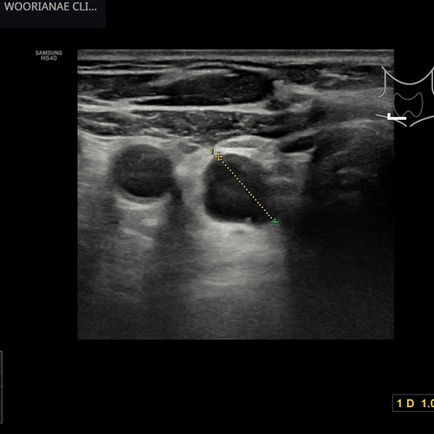

하복부, 골반 초음파; 난소종양

12시간 전

1분 분량